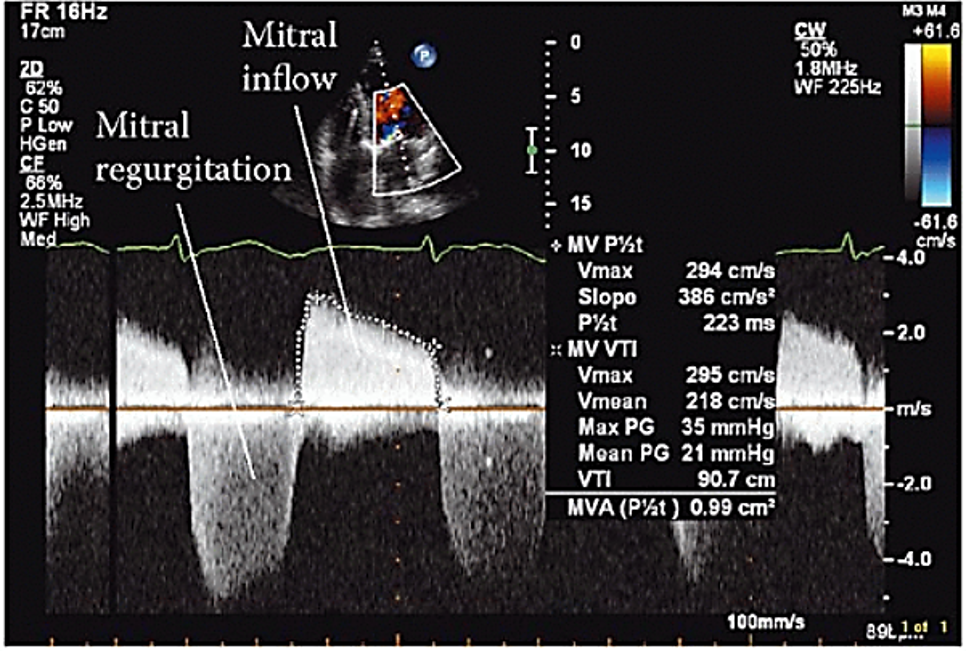

Pressure Half Time

The time it takes for the peak pressure to drop to half its original value